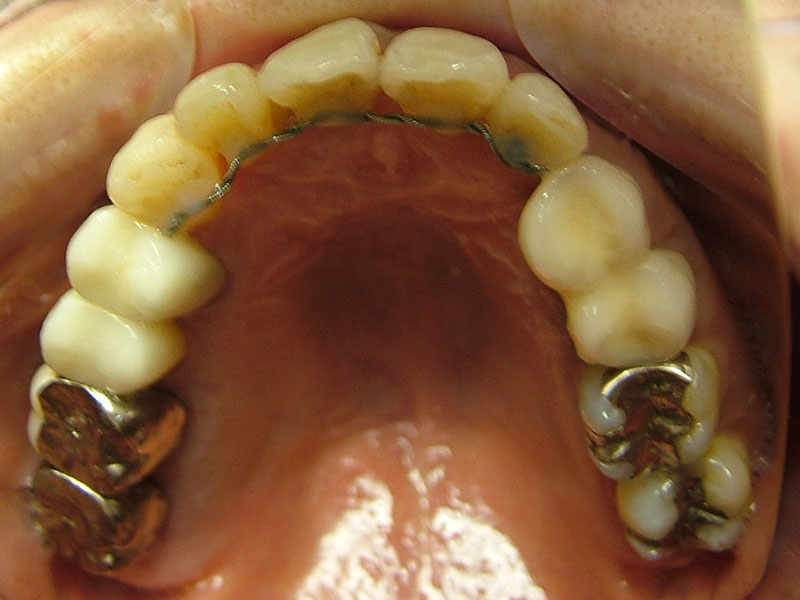

術前

- 初診:2006年。2010年―矯正治療を含めた一口腔単位の治療開始、治療当時、30代女性、喫煙者

- 主訴:虫歯治療、歯周病治療、できれば歯並びも治したい。

- 矯正診断:3級骨格性の反対咬合

- 治療方針:以前に治療した歯の再治療(虫歯治療、歯内療法、歯周処置)、右下前歯1本抜歯、矯正用インプラントを用いたワイヤー矯正、修復処置(被せ物)、保定(上ワイヤー、下マウスピース)、歯茎のピーリング(漂白)、4か月メンテナンス